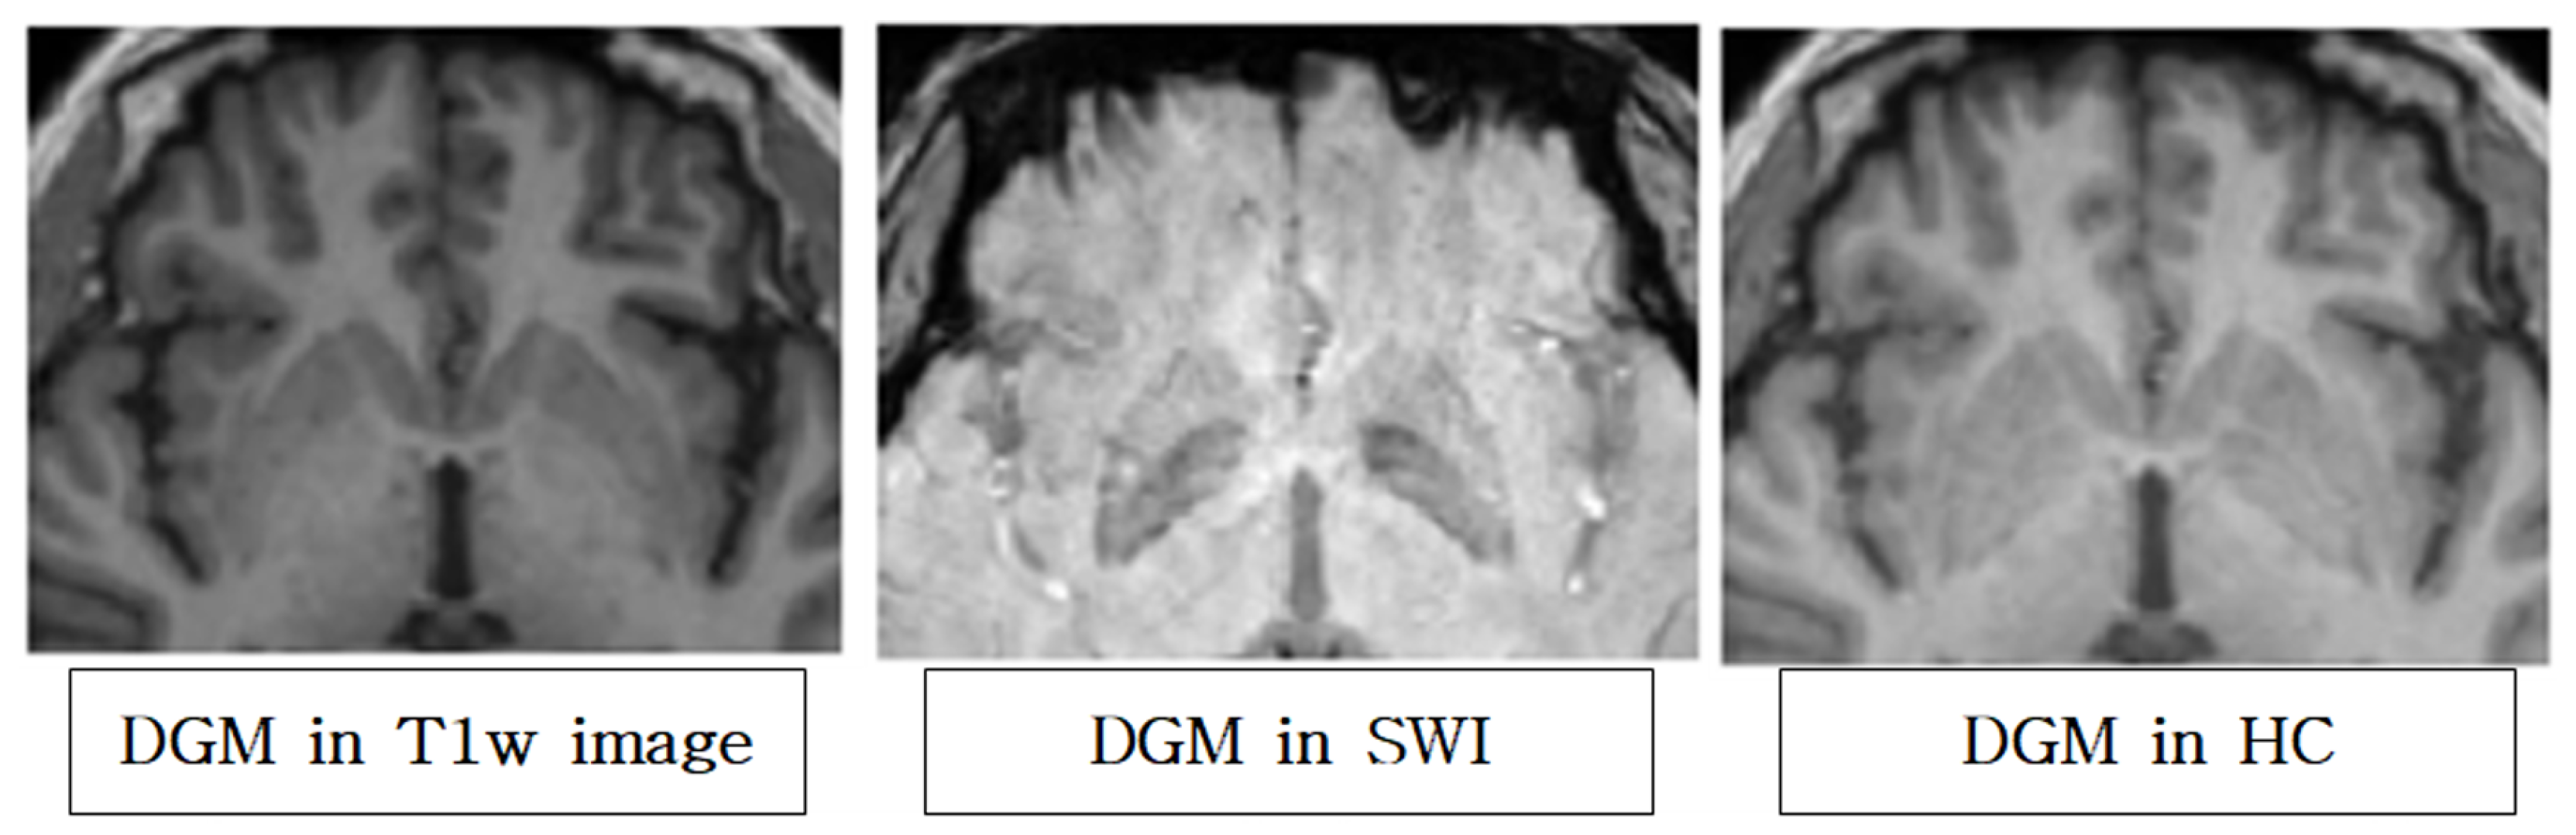

- We developed segmentation that reflects more the contrast of iron accumulation than conventional methods using a hybrid contrast image, which is created by image processing and combining T1w and SWI.

2.4. SWI Segmentation Using Hybrid Contrast Image